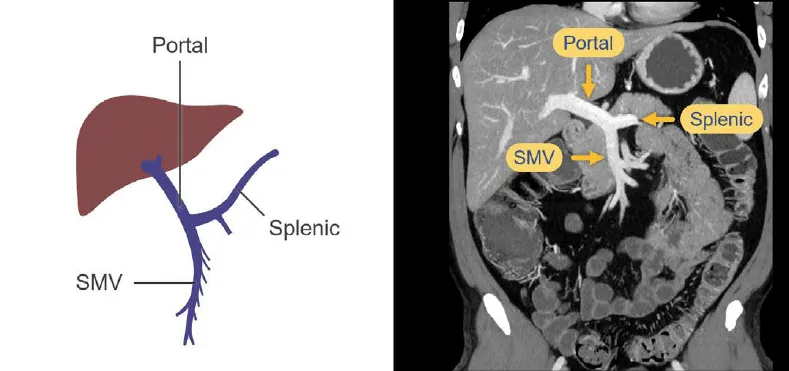

Portal Venous Phase (~60-90s): Optimal for abdominal viscera, especially the liver.

- Key Veins: Portal vein and its tributaries (Splenic Vein, SMV) are prominent.

- Liver: Reaches peak parenchymal enhancement, ideal for detecting hypovascular metastases.

⭐ Exam Favorite: The left renal vein courses between the SMA (anteriorly) and the Aorta (posteriorly). Compression here results in Nutcracker Syndrome, a cause of flank pain and hematuria.